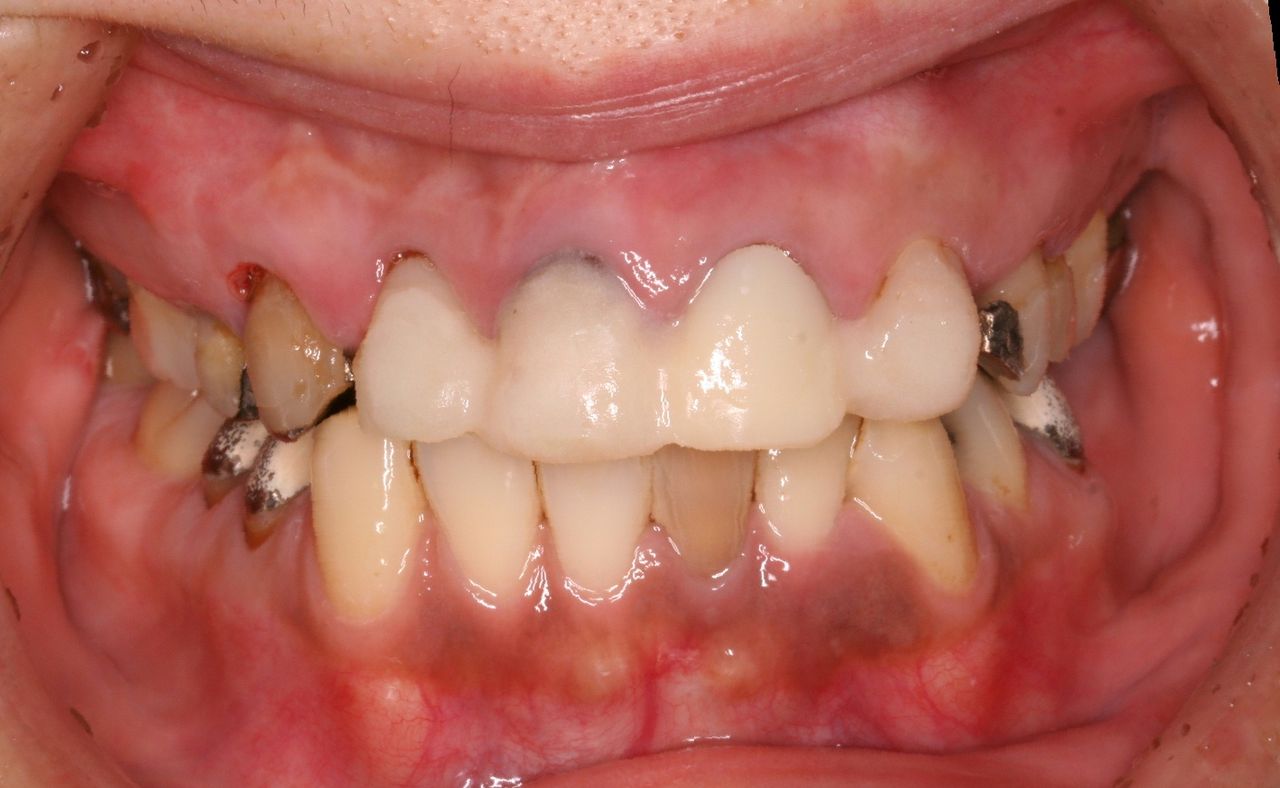

おそらく、数年前はきれいな差し歯が入っていたと推測されます。

正面からみると歯茎の黒ずみがきになります。原因は2つあり、ひとつは金属の土台から溶出される銀イオンです。もう1つは、歯を削るときにでる切削片が歯肉の中に入り込んでしまうのです。どちらも時間の経過とともに目立ってきますが、最近の審美治療ではこのようなことが生じません。

上から見ると、前歯はブリッジとなっており、左右1本づつ歯が欠損しております。

つまり、歯を抜いたのが左右1本ずつで、残りの歯をけずってブリッジにしております。